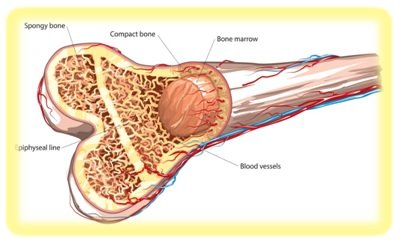

Stage 4: Cancer has advanced to distant organs, typically the lungs, liver, bones, or brain.